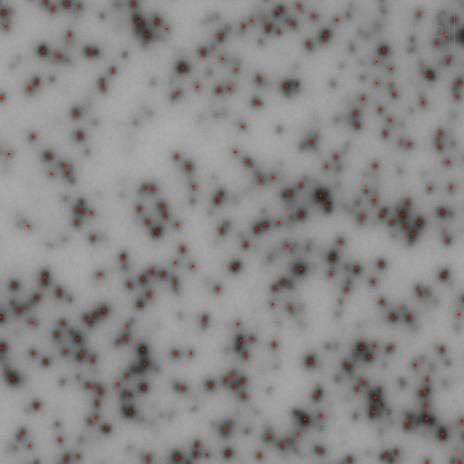

精確斑點定位

基于RAWSpot技術的精準定位,可以準確獲得斑點位置及對應細胞的分泌類型。

3.png  4.png

ELISpot斑點中心定位